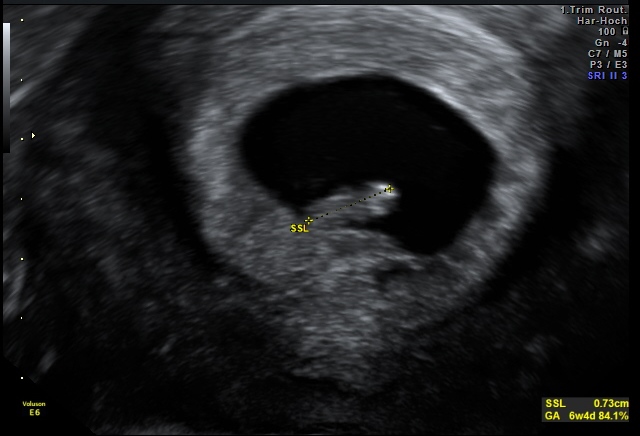

6w4d naša malá fazuľka ♥